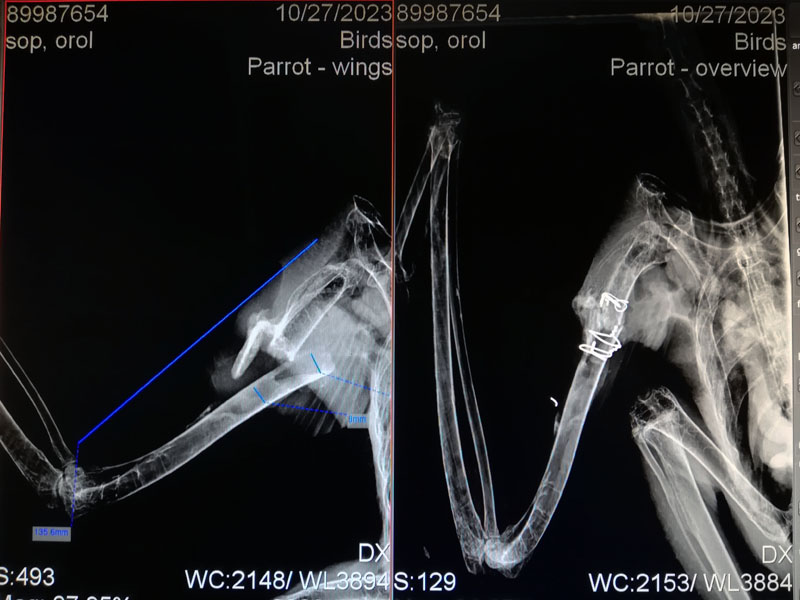

Pacientom bol mladý Orol kráľovský. Otrávil sa jedom na potkany, keď požral priotrávené hlodavce. Ako bol oslabený, zrazilo ho auto a utrpel zlomeninu ramennej kosti. Keď sa trochu pozviechal z otravy, bolo treba rýchlo zoperovať krídlo.

Typ a miesto zlomeniny sa priam nabádalo na použitie operačnej techniky s plastovým kolíkom vloženým do dreňovej dutiny kosti, ktorý sa následne zaistí proti posunutiu a rotácii oceľovými klincami a drátenými slučkami.

Takže som vysústružil zo Zedexu kolík (rozmery boli podľa odmerania kosti na rentgene)